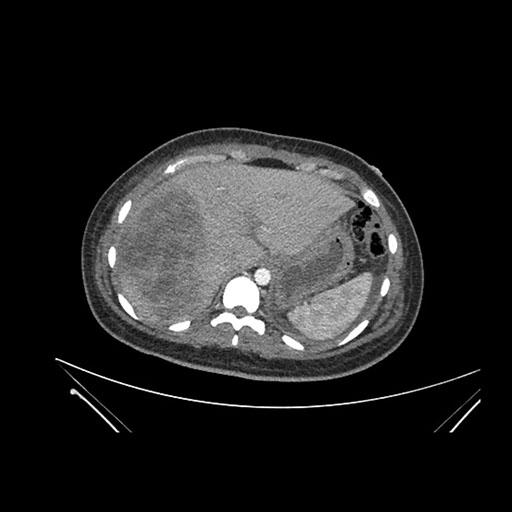

Imaging Analysis

Look through the patient's CT scan to identify any areas of concern for the necessary procedure.

Coronal Venous

Based on initial findings, which issue(s) would you be most concerned about?